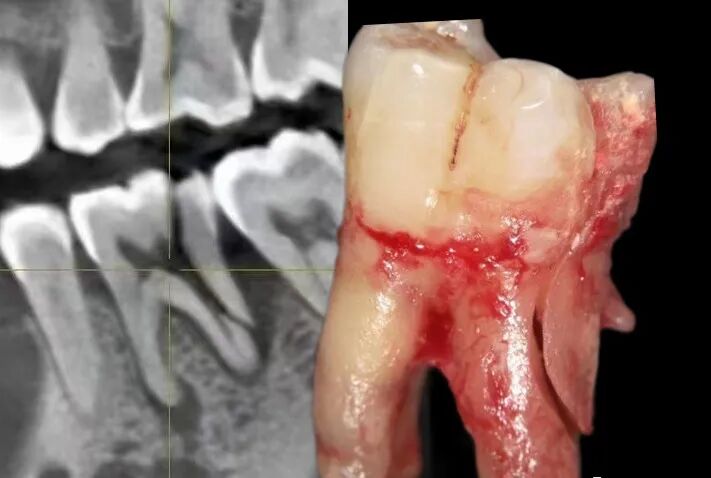

真实案例:下面这幅图片就是一个牙科医生发出来的一个患者的牙,之前做了“根管治疗”后,没有及时做“牙冠”,导致吃东西时把原来做过‘根管治疗’的牙直接劈成了2半,这不是既麻烦又难受?后悔都来不及了!!

经过根管治疗后的牙齿失去了来自牙髓的营养供应,就像失去树根的树木一样,慢慢枯萎变的很脆弱,造成牙齿的脆性增加,易劈裂。

于是抱着侥幸心理,让牙齿在没有“防护衣”的情况下:咬着小坚果,嗑着小瓜子……有一天,“咔”!牙齿劈裂了!